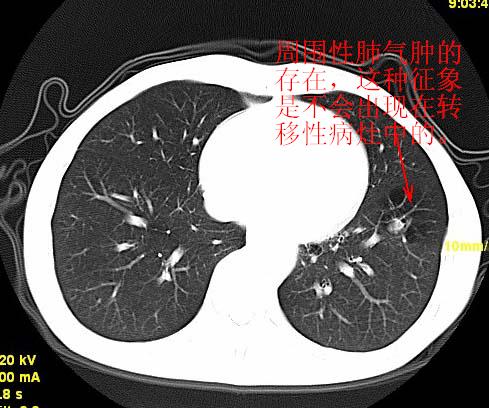

以下是引用wangzhengyuan在2007-11-11 23:31:00的发言:[br]钙化灶,看上去不像转移。

以下是引用zjzjr在2007-11-12 8:35:00的发言:[br]考虑错构瘤,建议定期复查.

以下是引用卜一在2007-11-12 5:59:00的发言:[br]病灶本身不像转移,不知有没有以前的胸部ct片,若有,则可以对比以下,若是新出现病灶,应高度警惕“转移”的可能![br]